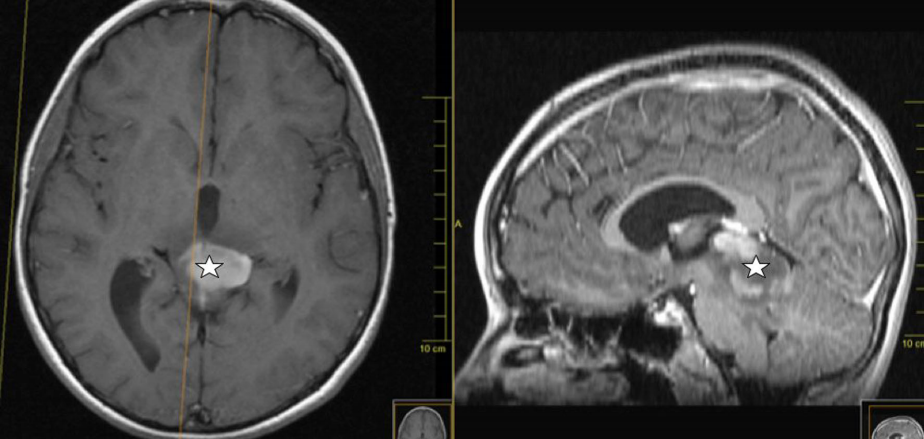

一名11歲男孩前來就診,診斷為四叉神經(jīng)板中線腫瘤,因雙側(cè)外展神經(jīng)麻痹而出現(xiàn)頭痛和復(fù)視的癥狀。檢查發(fā)現(xiàn)雙側(cè)乳頭水腫。頭部MRI檢查發(fā)現(xiàn)在頂蓋周圍有一中線病變,從小腦向松果體延伸,侵犯間腦(圖1和圖2)。在T-2加權(quán)成像中,病變呈均勻增強和高強度。脊髓MRI無異常。β-HCG以及α-fetoprotein都在正常范圍內(nèi)。經(jīng)內(nèi)窺鏡行腦室造口術(shù)。經(jīng)小腦上入路行枕下正中開顱,行病灶近全切除(圖3)。腫瘤組織切片提示有毛細(xì)胞性星形細(xì)胞瘤。與多個核發(fā)育異常的神經(jīng)節(jié)細(xì)胞以及神經(jīng)膠質(zhì)細(xì)胞有絲分裂活動和神經(jīng)節(jié)的部分可以在進一步組織學(xué)幻燈片演示(圖4)。較后組織活檢顯示在2-10%的位置顯示ki-67的性和突觸素染色,以及有絲分裂pHH3標(biāo)志。檢測到BRAF(V600E)突變。因此,診斷為間變性神經(jīng)節(jié)神經(jīng)膠質(zhì)瘤的III級。

圖1:術(shù)前矢狀面t2加權(quán)像顯示四叉神經(jīng)板高強度病變(星形),從小腦延伸至丘腦

圖2:術(shù)前軸位和矢狀位t1加權(quán)磁共振成像,對比顯示部分增強的低密度病變(星形)的四叉神經(jīng)板和雙側(cè)丘腦受累